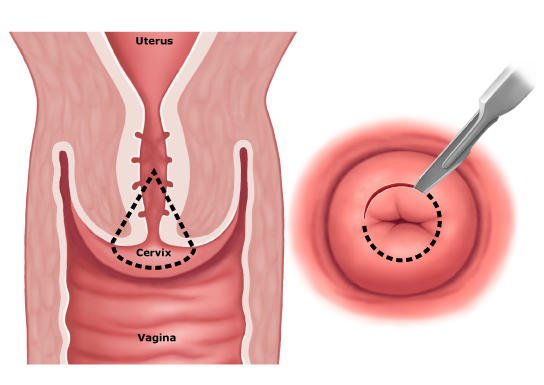

زگیلها پس از برداشته شدن برای بررسی به پاتولوژی فرستاده میشوند. برخی از زگیلها در زیر میکروسکوپ دچار تغییرات غیرطبیعی میباشند. به این تغییرات دیسپلازی مقعدی گفته میشود و با میکروسکوپ میتوان پیشرفت دیسپلازی یا تغییرات غیر طبیعی آنها را تعیین کرد. این تغییرات توسط پزشکان به نئوپلازی داخل اپیتلیومی با درجه بالا و درجه پایین تقسیم میشوند.

به سلول هایی که بدخیم یا پیش بدخیم میشوند، اما به عمق پوست حمله نمیکنند، نئوپلازی با درجه بالا گفته میشود. اگرچه این بیماری به احتمال زیاد پیشرونده به سرطان مقعد است، اما این سرطان مقعد نیست و متفاوت از سرطان مقعد درمان میشود.

دیسپلازی مقعد مشابه دیسپلازی دهانه رحم(نئوپلازی داخل اپیتلیومی دهانه رحم) است چرا که از یک عفونت مشابه ناشی از ویروس پاپیلومای انسانی منشا میگیرند و به ترتیب میتوانند به سرطان مقعد و گردن رحم پیشرفت کنند. بنابراین، بیماران مبتلا به دیسپلازی مقعدی نیاز به پیگیری دقیق توسط پزشک دارند تا هرگونه ضایعه جدید به سرعت ارزیابی شود. معاینه زنان و زایمان نیز در زنان توصیه میشود، زیرا وجود نئوپلازی داخل اپیتلیومی با درجه بالا، بیمار زن را در معرض خطر ابتلا به نئوپلازی داخل اپیتلیومی دهانه رحم نیز قرار میدهد.

آنوسکوپی با وضوح بالا به طور معمول شامل استفاده از رنگ های حاجب موقت (اسید استیک 3% و محلول ید لوگوول) داخل کانال مقعد است که به دنبال آن ارزیابی با میکروسکوپ با وضوح بالا انجام می شود تا به تشخیص بافت طبیعی از غیر طبیعی کمک کند. این روش بسیار شبیه به کولپوسکوپی (معاینه دهانه رحم) در خانمهایی است که دیسپلازی گردن رحم دارند. بیوپسیهای مسقیم از نواحی مشکوک و نیاز به درمان باید انجام شود.